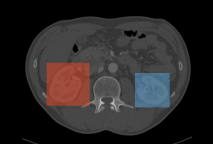

The results of applying a YOLOv3 object detection model are a series of 2D boxes around the objects of interest, as shown in the following examples.

Kidneys